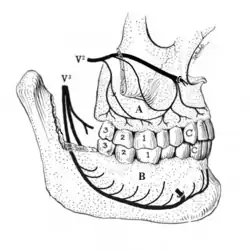

Disorders of the maxillary sinus can be referred to the upper back teeth. The posterior, middle and anterior superior alveolar nerves are all closely associated with the lining of the sinus. The bone between the floor of the maxillary sinus and the roots of the upper back teeth is very thin, and frequently the apices of these teeth disrupt the contour of the sinus floor. Consequently, acute or chronic maxillary sinusitis can be perceived as maxillary toothache,[36] and neoplasms of the sinus (such as adenoid cystic carcinoma)[37]: 390 can cause similarly perceived toothache if malignant invasion of the superior alveolar nerves occurs.[38]: 72 Classically, sinusitis pain increases upon Valsalva maneuvers or tilting the head forward.[39]

A tooth is composed of an outer shell of calcified hard tissues (from hardest to softest: enamel, dentin, and cementum), and an inner soft tissue core (the pulp system), which contains nerves and blood vessels. The visible parts of the teeth in the mouth – the crowns (covered by enamel) – are anchored into the bone by the roots (covered by cementum). Underneath the cementum and enamel layers, dentin forms the bulk of the tooth and surrounds the pulp system. The part of the pulp inside the crown is the pulp chamber, and the central soft tissue nutrient canals within each root are root canals, exiting through one or more holes at the root end (apical foramen/foramina). The periodontal ligament connects the roots to the bony socket. The gingiva covers the alveolar processes, the tooth-bearing arches of the jaws.[42]: 1–5